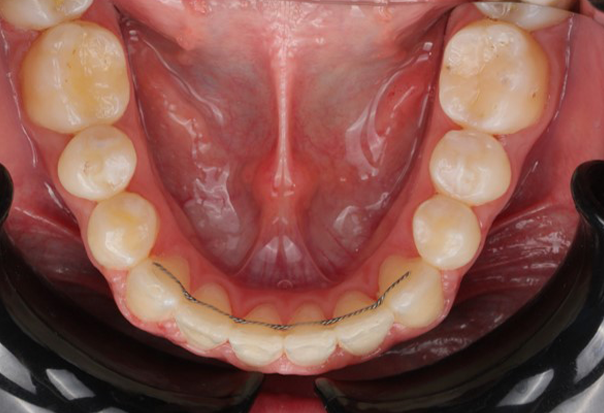

A 22-year-old female patient presented with a Class III malocclusion. She does not like her own profile. Her facial profile was straight with a slightly retrusive maxilla, the upper incisors were within normal inclination, and the lower incisors were retroclined. Bolton discrepency is on mandible for 6 teeth. A retruded upper lip and a normally positioned lower lip were noted. There was also a marked lack of midface support, and the constricted dental arches resulted in a narrow smile and pronounced dark buccal corridors.

At the end of treatment, the patient’s occlusion was corrected to Class I molar and canine relationships with a physiological overjet and overbite. Irregularities in both arches were eliminated, arch forms were coordinated, and incisor torque was effectively controlled to position the roots centrally within the alveolar bone, enhancing stability. Satisfactory intercuspation was achieved in both the anterior and posterior segments, with maintenance of midline coincidence and periodontal health throughout treatment. The case was finished and transitioned into the retention phase using fixed retainers in the maxillary and mandibular anterior regions.